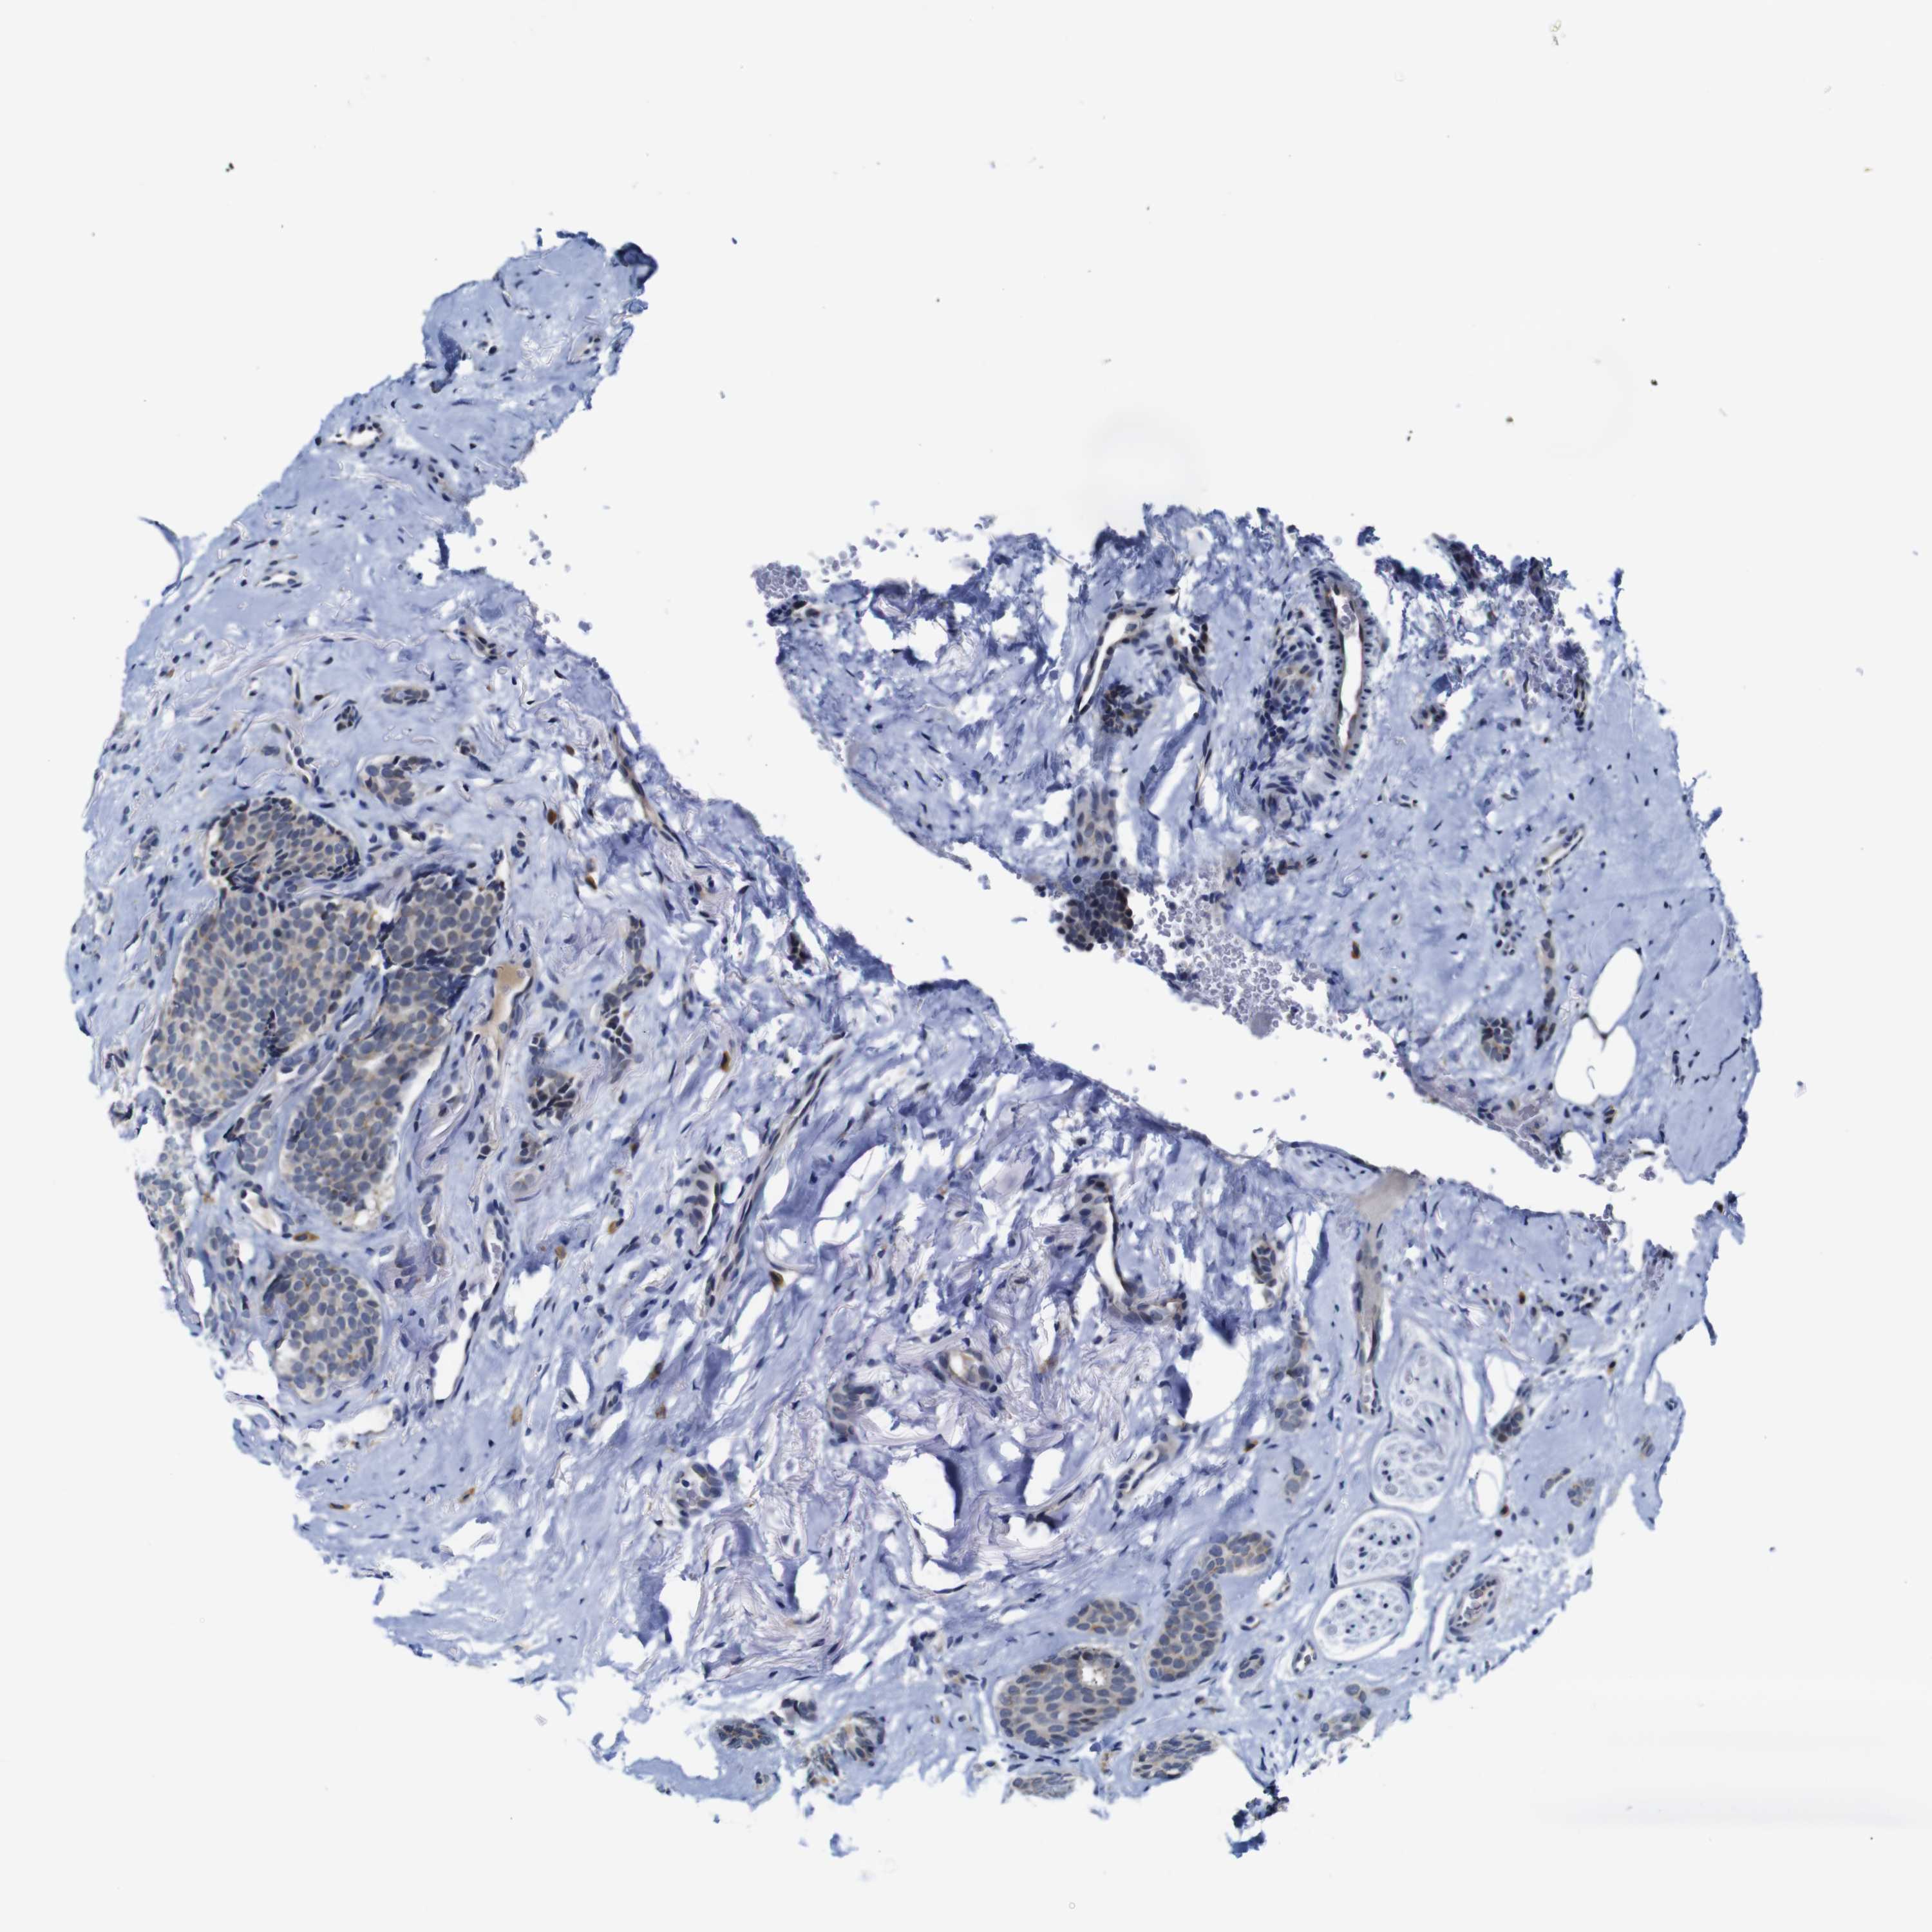

CANCER BREAST CANCER Show tissue menu

BRCA TCGA BRCA VALIDATION PROTEIN EXPRESSION

ANTIBODIES

AND

VALIDATION